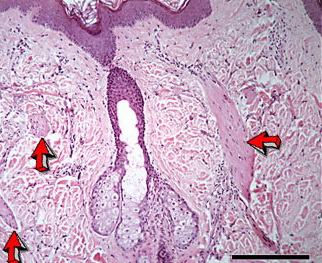

Read MoreSebaceous carcinoma = الكارسينوما الدهنية OLYMPUS DIGITAL CAMERA OLYMPUS DIGITAL CAMERA OLYMPUS DIGITAL CAMERA OLYMPUS DIGITAL CAMERA OLYMPUS DIGITAL CAMERA